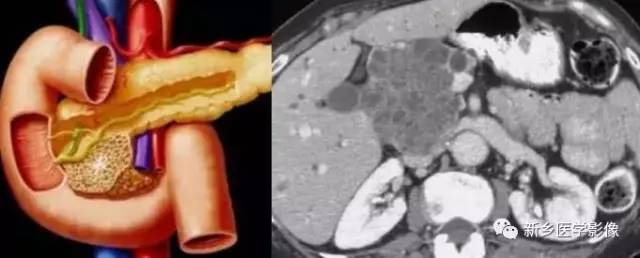

(一)浆液性囊腺瘤

为最常见的胰腺囊性肿瘤, 良性, 不发生恶变, 至今也未见原发性胰腺浆液性囊腺癌的报道。好发年龄30 ~ 50 岁, 女性多见, 男女比例1 ∶6 ~ 1 ∶9 。

一般无症状, 可有上腹部不适, 疼痛等, 有时可及肿块。浆液性囊腺瘤起源于胰腺中央的腺细胞, 根据囊的大小可分为三种类型, 即小囊型、大囊型和混合型, 其中以小囊型占绝大多数。